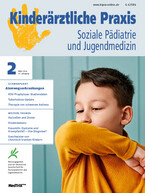

Endoskopisch (Abb. 1) zeigt sich eine unregelmäßige Ösophagusschleimhaut mit weißlichen Auflagerungen, die nicht abstreifbar sind. Es sind eine längliche Fältelung sowie eine Ringbildung erkennbar und die Peristaltik scheint vermindert. Histologisch (Abb. 2) zeigt sich ein hyperplastisches Plattenepithel mit ausgeprägter eosinophiler Ösophagitis (mind. 50 eosinophile Granulozyten bei 40-facher Vergrößerung). Somit besteht makroskopisch und histologisch das Bild einer eosinophilen Ösophagitis (eosinophilic esophagitis, EoE).

Bei klinischem Verdacht sollte eine Ösophagogastroduodenoskopie (ÖGD) mit Biopsien durchgeführt werden (Abb. 3). Typische makroskopische Veränderungen finden sich in ca. 90 % der Fälle [4]. Mögliche Befunde sind Ringbildungen, weiße Exsudate/Plaques, Längsfurchen, ein Schleimhautödem, Strikturen und eine Fragilität der Mukosa [1, 3, 4]. Histologisch finden sich eine Eosinophilie mit > 15 Eosinophilen/high power field (HPF), eosinophile Mikroabszesse sowie unspezifische Veränderungen, wie beispielsweise eine Basalzonenhyperplasie [5]. Laborchemisch kann teilweise eine Eosinophilie im peripheren Blut gemessen werden [6], diese ist jedoch nicht immer vorhanden und lässt sich aufgrund der häufig zusätzlich bestehenden atopischen Erkrankungen nicht sicher der EoE zuordnen. Nach einer 8-wöchigen Therapie mit Protonenpumpeninhibitoren (PPI) in einer Dosierung von 1 – 2 mg/kg/Tag (maximal 40 mg/Tag) muss erneut eine ÖGD mit Biopsien erfolgen. Erst wenn hier histologisch weiter > 15 Eosinophile/HPF in der Ösophagusschleimhaut detektiert werden können, kann die Diagnose einer EoE gestellt werden. Bei einer Reduktion der Eosinophilen nach PPI-Therapie auf < 15 Eosinophile/HPF müssen andere Differenzialdiagnosen, z. B. eine PPI-responsive EoE oder eine gastroösophageale Refluxerkrankung (gastroesophageal reflux disease, GERD), in Betracht gezogen werden.

- Histologische Eosinophilie (> 15 Eosinophile/HPF)

Unser Patient

Bei unserem Patienten begannen wir nach Erhalt der Befunde eine Therapie mit Omeprazol 40 mg/Tag für 8 Wochen. In einer anschließenden Re-Endoskopie zeigte sich zwar makroskopisch eine leichte Besserung der Befunde, es waren jedoch immer noch typische Veränderungen einer EoE (hier insbesondere eine Längsfurchung sowie weißliche, punktförmige Erhabenheiten und ein typisches Ablederungsphänomen bei Biopsierung aufgrund der pergamentartigen Schleimhaut) vorhanden. Auch histologisch persistierte die Eosinophilie mit > 50 eosinophilen Granulozyten/HPF in der Ösophagusschleimhaut. Wir veranlassten eine umfassende allergologische Diagnostik zur Identifikation möglicher auslösender Antigene. Weder das Gesamt-IgE noch der spezifische ImmunoCAP auf Nahrungsmittelallergene (Eiklar, Milcheiweis, Dorsch (Kabeljau), Weizenmehl, Erdnuss, Sojabohne, Haselnuss, Karotte, Sellerie) zeigten pathologische Werte.